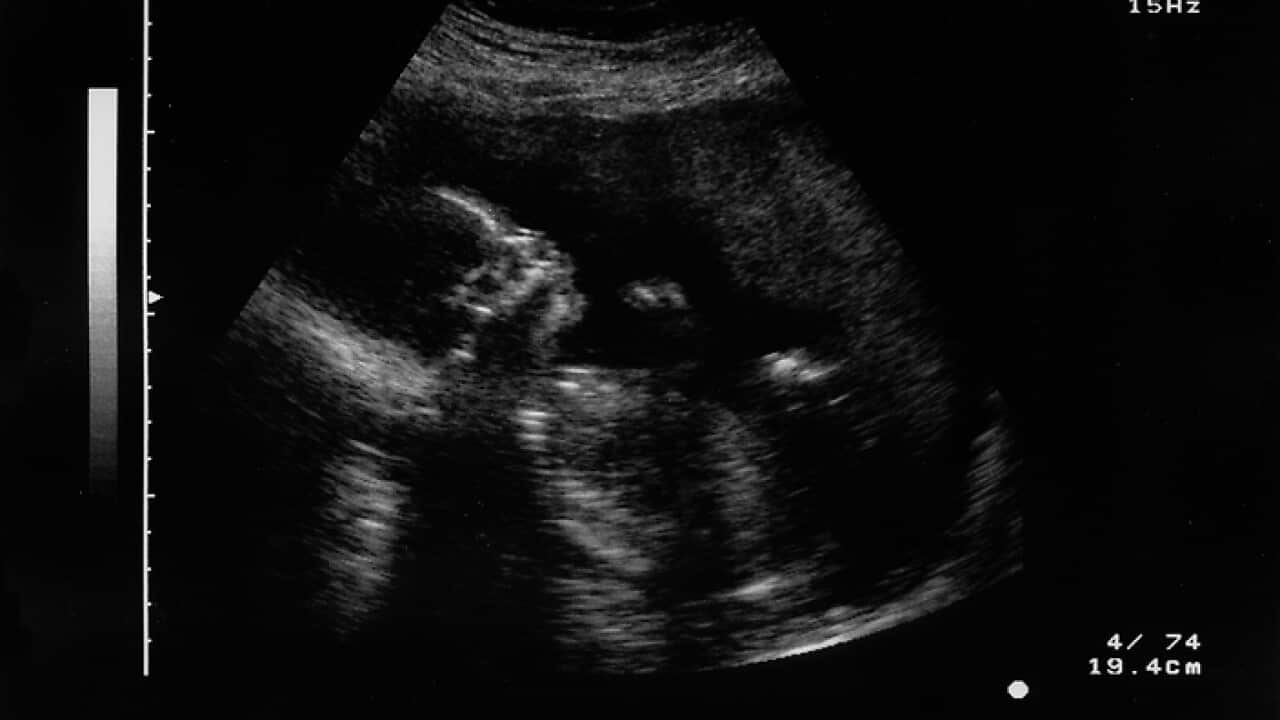

This area of research involves developing a new software based on machine learning, which could potentially help in detecting those abnormalities that are often missed in routine ultrasound examinations that are taken within the first 20 weeks of pregnancy.